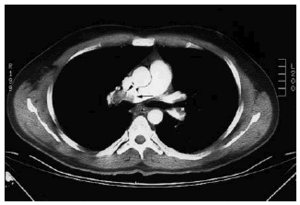

Se le practicó tomografía axial computarizada (TAC) helicoidal, que demostró la presencia de trombos en la luz del tronco principal de la arteria pulmonar derecha (fig. 1) y en la rama inferior de la arteria pulmonar izquierda (fig. 2).

Fig. 2.